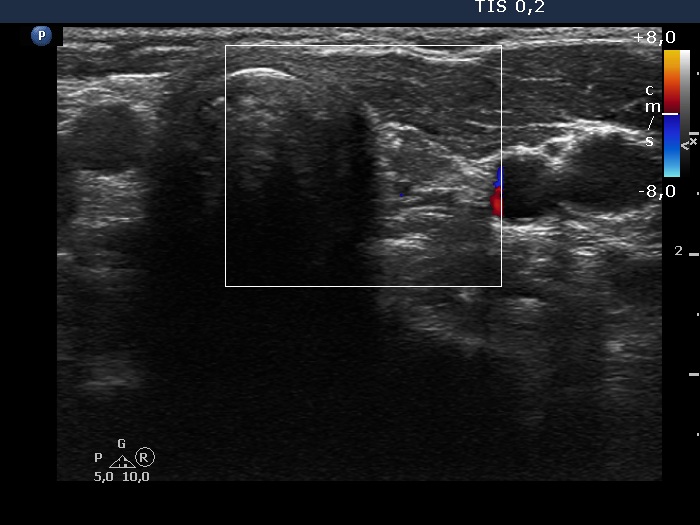

Left lobe, transverse view, color Doppler mode. The lesion shows no vascularity.